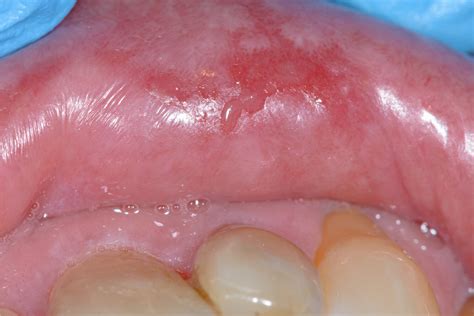

The primary symptom that sets this condition apart is the intense pain associated with the erosions. Patients often describe a burning sensation that intensifies when they consume acidic, spicy, or hot foods. The appearance can be quite alarming, often presenting as:

• Bright red patches: Areas where the outer layer of the mucosal lining has been shed.

• Ulcerations: Open, raw sores that bleed easily.

• White striae: Lacy, web-like white lines surrounding the red or ulcerated areas.